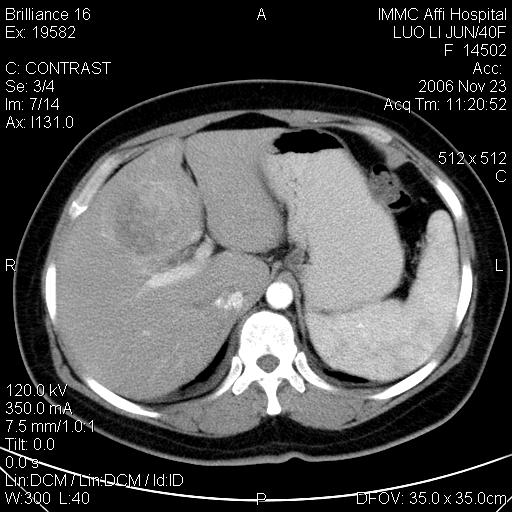

标题: CT5664:我也发一个肝脏的片子大家看看

很典型的肝癌。

速升速降,典型肝癌.

支持-----考虑肝癌----[-从片上看增强早期应该是动脉晚期即门脉早期]

是啊,典型的早出早归!

快进快出典型肝癌.

符合肝癌的增强特征。支持肝癌!

病灶好圆!可能恶性度不高。

不能除外肝细胞腺瘤吧,还是得结合病史。

很好的片子,可惜增强做的比较失败,a期时间没有把我好,实际到了静脉早期了,否则会更典型。

最终考虑是肝腺瘤